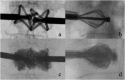

Vertebral fracture (VF) is a common condition with >160,000 patients affected every year in North America and most of them with affected lumbar vertebrae. The management of VF is well known and defined by many protocols related to associated clinical neurological symptoms, especially in case of the presence or absence of myelopathy or radicular deficit. In this article, we will explore the percutaneous stabilization of the lumbar spine by showing the newest approaches for this condition.